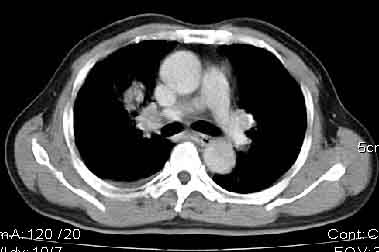

该病例我的诊断意见:右肺上叶周围型肺癌伴纵隔和右肺门淋巴结增大和右肺上叶阻塞性肺炎{病灶周围致密影以近肺门侧明显!}。右侧少量胸腔积液。

一. 1)症状有无发热及慢性过程.2)化验室检查?3)有无tb接触史?二.右肺上叶见片团状影,边界欠清,外侧方见一结节状软组织影,密度欠均匀,内可见低密度坏死区.周围强化明显,肺内见纤维索条影,局部胸膜增厚,但无明确胸膜凹陷.上叶支气管壁增厚,肺门及纵隔淋巴结增大.右侧胸腔少量积液.诊断意见:1右肺上叶慢性感染性疾病(肺tb?)伴肺门,纵隔淋巴结大.右胸少量积液.右肺上叶结节影多为tb球?2右肺上叶周围型肺ca伴肺门,纵隔淋巴结转移待排.右肺上叶炎变(肺门及纵隔淋巴结压迫).右胸少量积液.等待随返结果.